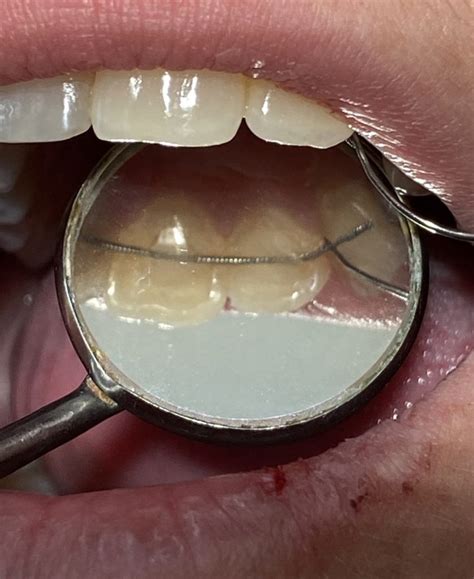

@andreabecerraortodoncia Como se adapta un #retenedor fijo #brackets #odontologia #ortodoncia

Retenedor Dental Fijo

Un retenedor dental fijo consiste en un alambre metálico delgado, hecho a medida, que se adhiere a la parte posterior de tus dientes. Permanece invisible y previene eficazmente el movimiento no deseado de los dientes sin afectar a tus actividades como beber, comer y hablar. Una vez colocado, permanece en su lugar durante años, y no tienes que preocuparte por su uso.